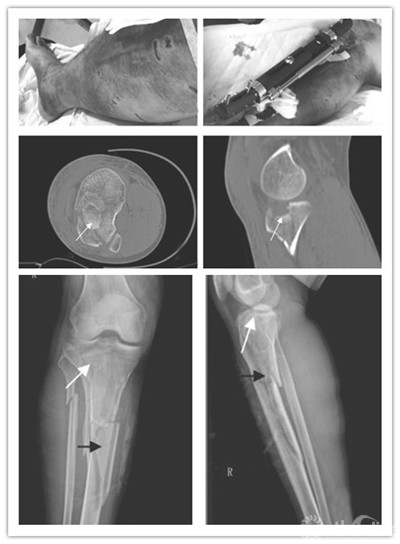

图1 右胫腓骨粉碎性骨折(男性患者,31 岁;车祸伤致右胫腓骨粉碎性骨折、外侧平台塌陷、右下肢软组织严重挫伤;A、B:右下肢肿胀明显、皮下瘀血;C、D:CT 平扫,白箭头示胫骨外侧平台塌陷骨块;E、F:X线平片,黑箭头示胫骨干粉碎性骨折)